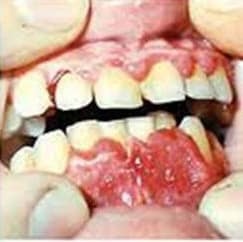

Imaginile arata dezvoltarea bolilor inflamatorii ale gingiilor: mucoasa primul afectat (gingivite) apoi parodonțiu, apoi coborâte gingiile și dinții devin liber.

Fotografii - gingivita ca guturai

Fotografii - forma edematoasă a gingivitei hipertrofice